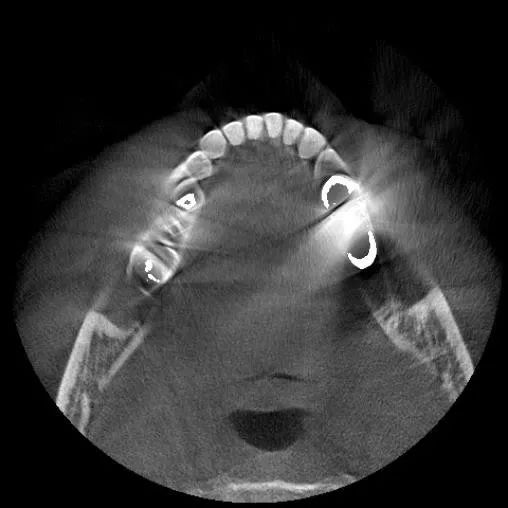

影响对比

为了解决难题,田方俊1年里8次前往美国芝加哥大学医学院,希望得到医学影像、图像重建算法等领域的权威专家的帮助。“我当时一心想打造属于中国人的民族品牌,也许是我的这份坚持打动了专家,我们的研发团队和专家团队在美国共同设立研发中心,最终我们的核心图像重建算法研究有了质的突破。”田方俊介绍。